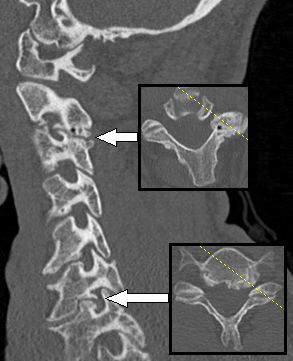

При спондилёзе костная ткань суставов разрастается, образуются остеофиты, то есть дополнительная костная ткань (по мере нарастания костный вырост распространяется к соседнему позвонку, тогда как от соседнего позвонка образуется такой же вырост, в некоторых случаях окостенение начинается на уровне межпозвоночного диска). В особо тяжёлых случаях наступает сращение позвонков, от чего страдают сосуды, нервы и мышечная ткань, а также близлежащие органы[4].